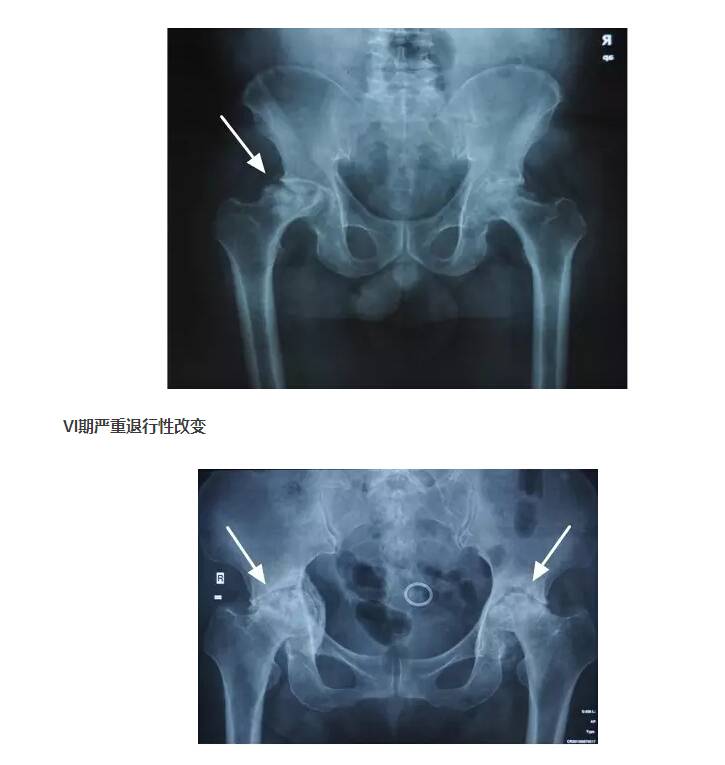

IV期X线片显示股骨头变扁

IV期、V期和VI期的患者,由于股骨头坏死已经导致股骨头塌陷变形,所以只能行全髋关节置换术。并且尽量在VI期以前完成手术,因为一旦髋臼出现严重磨损、骨缺损,会显著降低人工关节假体的稳定性和使用寿命。人工关节置换手术以后第二天就可以下地行走,可以下蹲和跑步,不再需要服用药物,生活同常人无异。